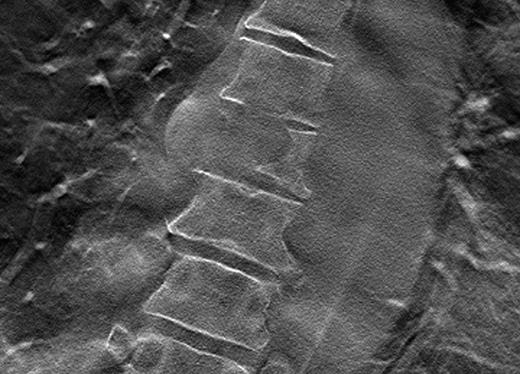

Sample lytic lesions on DT: